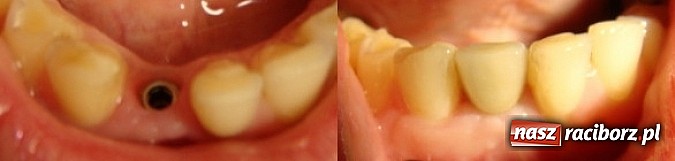

Dlatego też coraz większą popularność zdobywają implanty. - Zastosowanie implantów nie wymaga ingerencji w pozostałe zdrowe zęby. Ponadto implant najwierniej odzwierciedla ząb naturalny, i to zarówno pod względem estetycznym, jak i funkcji fizjologicznych – tłumaczy specjalista z Dentica Bieleccy. Implant to śruba, najczęściej tytanowa, która odtwarza korzeń utraconego zęba. To znakomite rozwiązanie w przypadku utraty pojedynczego zęba, chociaż coraz więcej osób decyduje się wymienić „sztuczną szczękę” na implanty.

Śruba zastępuje korzeń

Technologia implantologiczna nieustannie się rozwija. Obecnie dostępne są implanty ze specjalnymi powierzchniami, przyśpieszającymi proces zespolenia kości z tytanową śrubą. To skraca czas całego leczenia, który trwa co najmniej 3-4 miesiące. Ale spokojnie, bo nie oznacza to, że na ten czas musimy się zaszyć w czterech ścianach i zasłaniać twarz!

Ze względów estetycznych, na czas leczenia stosowane są protezy zastępcze. - Na przykład mosty adhezyjne przyklejane do zębów sąsiednich, protezy ruchome podparte odciążające miejsca wszczepienia implantów lub zastępcze korony, ale tylko wtedy, gdy wszczepiony implant jest stabilny – wymienia dr Bielecki.